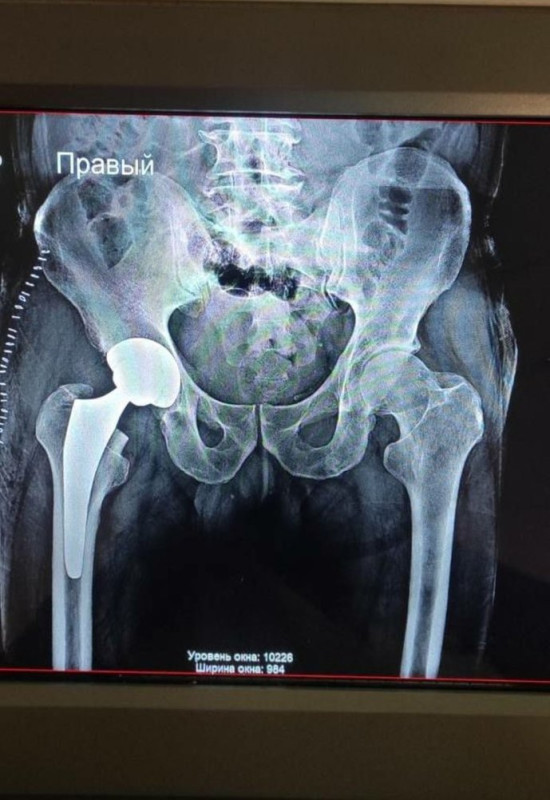

"Кам’янець-Подільська міська лікарня, Слобідко-Кульчієвецька, Волочиська багатопрофільна лікарня, Хмельницька міська лікарня, Хмельницька обласна лікарня, Шепетівська багатопрофільна лікарня. Вони віднесені до лікарень, які займаються ендопротезуванням колінних, кульшових суглобів. Наразі в черзі у Хмельницькій області перебуває 216 пацієнтів".

В область надійшло 279 кульшових ендопротезів різних розмірів та 60 колінних для безкоштовної заміни пацієнтам. Суспільне Хмельницький

За словами Дениса Дудко, в область надійшло 279 кульшових ендопротезів різних розмірів та 60 колінних. НСЗУ оплачує вартість роботи лікарів-травматологів, ліків, а ендопротези централізовано закуплені за державні кошти.